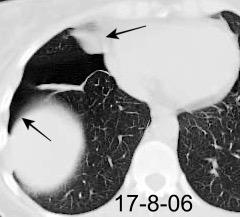

Marzo 2014: Perforación longitudinal distal secundaria a episodio de vómito (síndrome de Boerhaave). Derrame pleural izdo. que evoluciona a empiema.

Wang C-T et al. Tension hydropneumothorax in a Boerhaave syndrome patient: A case report . World J Emerg Med, 2021. Katabathina V et al. Nonvascular, nontraumatic mediastinal emergencies in adults:a comprehensive review of imaging findings. Radiographics. 2011.